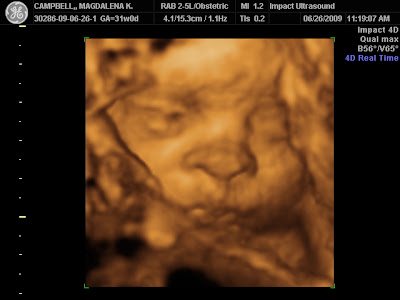

Today we returned for another 4D ultrasound of the baby, this time we tried a different tactic. They recommend the mother drink some fruit juice 30 minutes before the session to make sure the baby will be moving and active. Well Lola has been nothing but active throughout the pregnancy, so we skipped the juice hoping she'd be a bit more still, allowing better pictures of her face.

Our plans were thwarted by Lola's love of nestling into the placenta and her apparent love of sticking her hands and feet in front of her face. At one point she had her big toe stuck in her nostril! We got to see lots of live shots of her yawning and opening her eyes, very cool, but the great full face shot eluded us this time. We've posted a few of the better pictures.